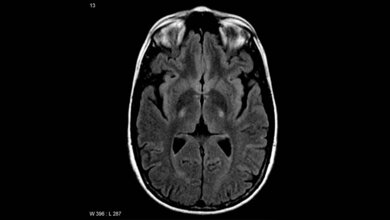

Stephen Hawking ist vielleicht der berühmteste Patient, der an ALS litte. Einer breiten Öffentlichkeit bekannt geworden ist die Krankheit durch die Ice Bucket Challenge, die in den sozialen Medien seinerzeit eine große Aufmerksamkeit erzielte. Insgesamt leiden weltweit circa 150.000 Menschen an der Amyotrophen Lateralsklerose (ALS). Sie wird auch als Motoneuronen-Krankheit bezeichnet. Bei ALS nimmt die Bewegungsfähigkeit der Patientinnen und Patienten im Laufe der Zeit ab und kommt zum Stillstand. Gleichzeitig bleibt die Aktivität des Gehirns komplett funktionsfähig. Der Bioinformatiker Schönhuth entwickelt in seiner Arbeitsgruppe Genome Data Science (Genom-Datenwissenschaft) Methoden und Werkzeuge, um mit Zehntausenden von Genomen zu arbeiten und die Daten zu analysieren. Die Arbeitsgruppe gehört neben der Technischen Fakultät auch zum Centrum für Biotechnologie (CeBiTec) der Universität Bielefeld.